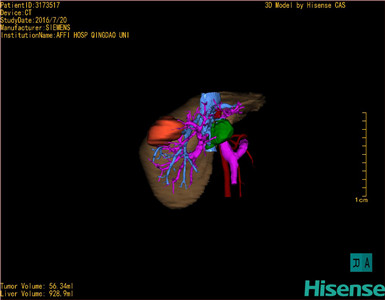

肝细胞肝癌-CH-001-LT-000341

将0.625mm双源薄层CT资料的静脉期和动脉期Dicom格式文件导入海信CAS系统。

通过调节窗宽窗位调整CT序号,对肿瘤,肝实质,胆囊,下腔静脉,肿瘤,肝动脉、门静脉及肝静脉等进行三维重建;系统自动计算肿瘤体积和肝脏体积。

模拟手术操作,自动计算切除肿瘤体积。肝脏体积为928.9ml,肿瘤体积为56.34ml,肿瘤体积为肝脏体积的6%,通过比对60-70岁正常肝脏体积为1262.7±284.31 ml,通过术前模拟手术,精准判断切除后剩余肝脏体积能耐受,避免肝衰竭发生。

术前手术方案的规划。

术前三维重建:

重建图片